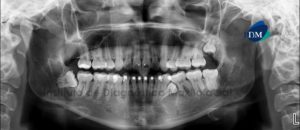

Paciente masculino de 15 años de edad que es referido para la evaluación de los terceros molares. La radiografía panorámica nos muestra la presencia de